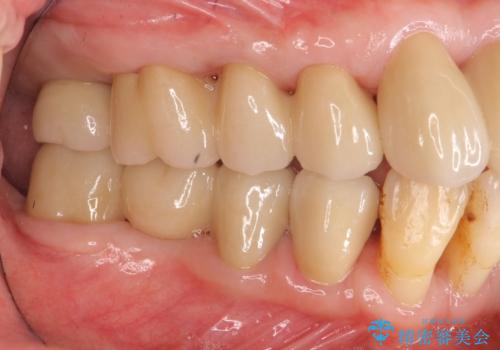

インプラント治療に加え、歯周病に対しての再生治療や歯周ポケットの除去を行う歯周外科、矯正治療、と必要な治療は多岐に渡りましたが、最終的に安定した噛み合わせを得られたとともに、清掃のしやすい口腔内環境を確立できました。